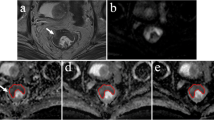

The MRI images were independently reviewed by the two radiologists (Y.Y. and H.L., 4 and 10 years of experience in reading rectal MRI) who were blinded to the patients’ clinical and pathological information but were aware that the patients had been diagnosed with rectal cancer. To measure the ADC of the tumor, the largest tumor cross section was selected on the ADC map. Regions of interest (ROIs) were applied to intratumoral and peritumoral zones (Fig. 1). The radiologists reviewed the T2WI and DWI images and determined the location of the tumor. According to the previous method described by Mori et al [16], three elliptical ROIs (mean area, 20 mm2) were then drawn along the tumor margin where the ADC values visually appeared to be most increased on the peritumoral zone for measuring the ADC values of the individual ROIs: the maximum mean values of these ADC were designated as the peritumoral ADC (ADCpmean). For intratumoral ADC measurements, ROIs were placed inside the tumor that contained the largest tumor area, while cystic, necrotic, and visible vascular structures were carefully avoided by referring to T2-weighted images. Maximum, minimum, and mean values of intratumoral ADC were recorded and designated as ADCtmax, ADCtmin, and ADCtmean, respectively. The peritumor-tumor ADC ratio was calculated according to the following formula: ADC ratio= ADCpmean/ADCtmean.

Methods used to measure the tumor and peritumor apparent diffusion coefficient (ADC) values. A–C A 61-year-old man with T3N2M0, extranodal extension (ENE)–positive, tumor deposit (TD)–positive, lymphovascular invasion (LVI)–positive, and poorly differentiated rectal cancer. Regarding the tumor ADC, the slice with the largest tumor cross section was selected, and the region of interest (ROI) was placed inside the tumor that contained the largest tumor area with reference to (A) T2WI imaging and (B) DWI. ADCtmax, ADCtmin, and ADCtmean are recorded as 0.919 × 10−3 mm2/s, 0.668 × 10−3 mm2/s, and 0.833 × 10−3 mm2/s, respectively. For the peritumoral ADC, three elliptical ROIs were drawn along the tumor margin where the ADC values visually appeared to be most increased in the (C) peritumoral zone. The maximum mean value of the three ADC values was designated as the peritumoral ADC (ADCpmean). The ADCpmean and ADC ratio are 2.033 × 10−3 mm2/s and 2.441, respectively. D–F A 65-year-old woman with T3N1M0, extranodal extension (ENE)–negative, tumor deposit (TD)–negative, lymphovascular invasion (LVI)–negative, and moderate differentiation rectal cancer. The ADCtmax, ADCtmin, ADCtmean, ADCpmean, and ADC ratio were recorded as 1.124 × 10−3 mm2/s, 0.690 × 10−3 mm2/s, 0.891 × 10−3 mm2/s, 1.649 × 10−3 mm2/s, and 1.851, respectively